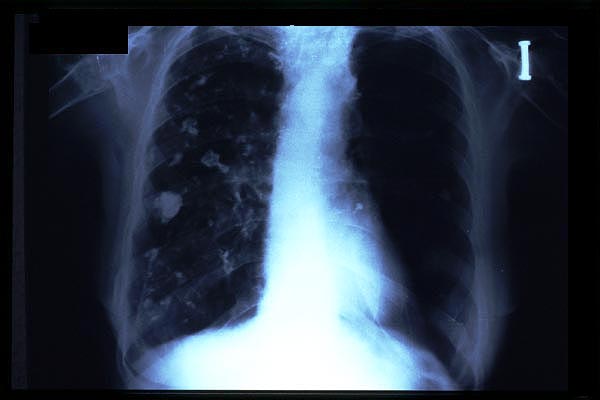

TBC pulmonar antigua